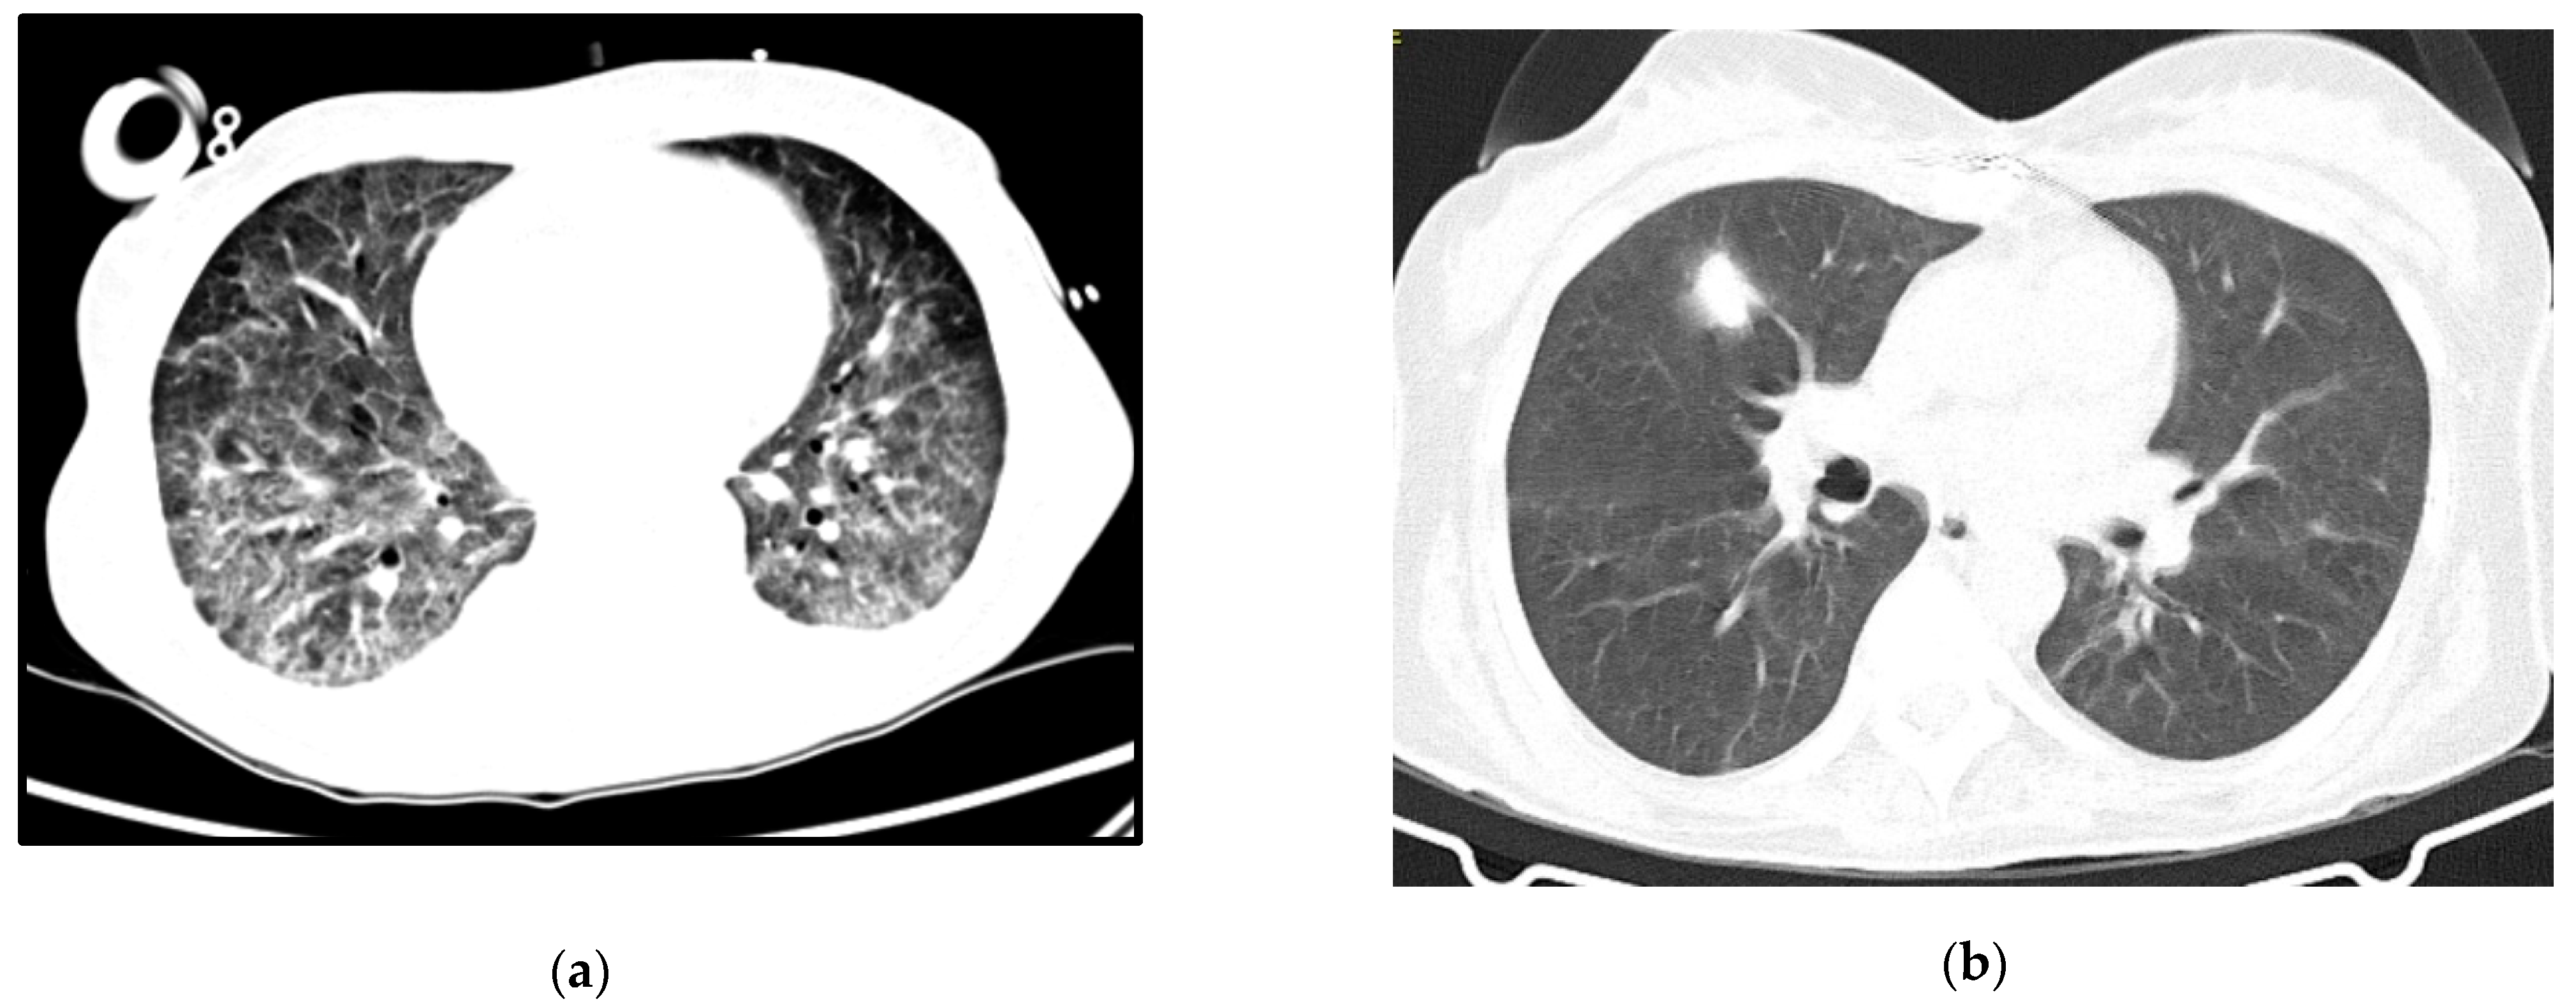

A 53-year-old woman, with no relevant medical history so far, was brought to the ER due to a two-month history of progressive psychomotor slowness and confusion, which had worsened in the week before. At physical examination, she was agitated and febrile. Head CT scan showed some intra-axial lesions in the left frontal and temporal lobes. The cerebral spinal fluid (CSF) had mild pleocytosis and moderately elevated proteins. The serology for HIV was positive, and the nucleic acid test of the CSF was positive for toxoplasma gondii. She was admitted in the ICU with a de novo diagnosis of HIV infection, with severe immunosuppression (CD4+ count 28 cells/mm3), clinically manifested as cerebral toxoplasmosis. On day 3, she began coughing, with respiratory hypoxemic insufficiency and bilateral diffuse glass opacities on chest-CT scan (Figure 3a). The presumptive diagnosis of PJP was posteriorly confirmed with both direct dye-examination and PCR positive for P. jirovecii in BAL. She was treated with TMP-SMX for both PJP and cerebral toxoplasmosis. Following one week of appropriate medical treatment, the patient had a favorable response, and was discharged to the ward for further care.

At the end of the month, she was readmitted to the ICU because of respiratory failure and elevated lactate. Respiratory secretions and gastric aspirate were both negative for tuberculosis. Other microbiology tests (including blood serologies for other common opportunistic agents) were also negative. She repeated chest-CT, and had severe deterioration in the lung opacities, with bilateral consolidation described as possible ARDS and/or nosocomial infection. As she showed no signs of clinical improvement despite corticosteroids and High Flow Oxygen Therapy (HFOT), she was intubated, had a repeat bronchofibroscopy and started broad spectrum antibiotics.

The patient developed septic shock and ARDS with refractory hypoxemia and she was put on VV-ECMO. The indirect immunofluorescence was positive for P. jirovecii in BAL. She completed 21 days of treatment for PJP and 7 days of piperacillin- tazobactam, with respiratory improvement. ECMO was stopped after 12 days.

Persistent fever and elevated inflammatory markers ensued, with isolation of multidrug-resistant Pseudomonas aeruginosa in respiratory secretions. Chest X-ray confirmed lobar nosocomial pneumonia. She started a targeted antibiotic course with cefepime, with good clinical, analytical, and radiological response. Roughly one week later, she was extubated to non-mechanical ventilation, and rapidly weaned off respiratory support to no oxygen supplementation. The evolution in her condition can be seen at the images in Figure 3b.

She was discharged to the ward after one month of ICU stay for muscular rehabilitation, already on antiretroviral therapy and free of acute infectious complications.

Figure 3. Case 3 thoracic CT-scan at diagnosis (a) and follow-up (b).